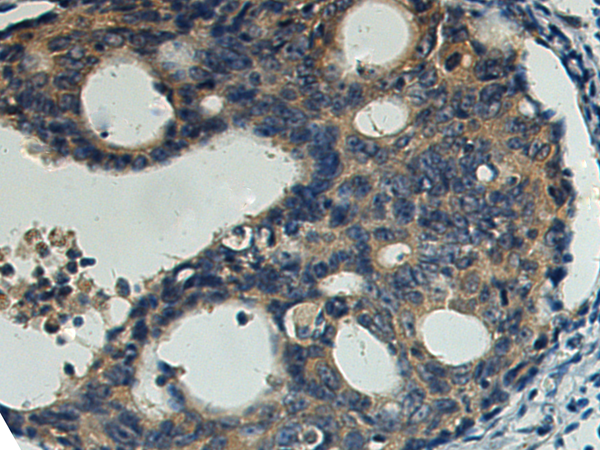

分类: 科研抗体货号: P07320别名: CSF; GMCSF应用: WB,IHC反应种属: Human